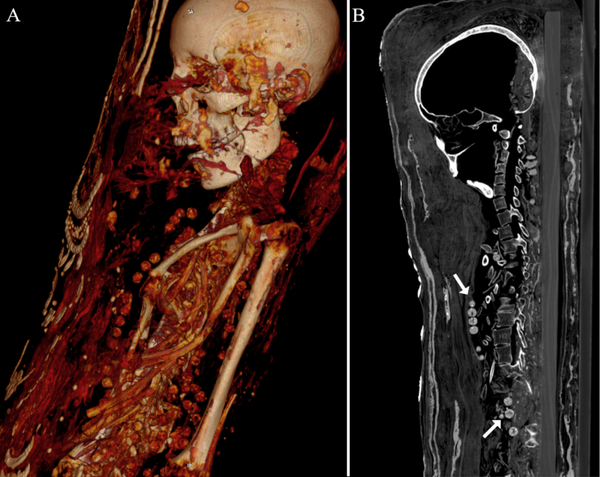

Agora, tomografia computorizada revelou que ao menos uma das três múmias foi enterrada com os órgãos (até o cérebro) e que as duas mulheres foram enterradas com belos colares, encontrados pelos pesquisadores.

Além disso, tomografia computorizada mostrou que depois da morte dessas pessoas, suas múmias foram enterradas com artefatos que podiam ser úteis na vida após a morte, inclusive moedas.

As múmias, depois de passarem por vários donos, acabaram nas Coleções de Arte de Dresden, na Alemanha, onde foram submetidas a raios-X no fim dos anos 80. No entanto, tomografia computadorizada revelou muito mais sobre o interior das múmias.